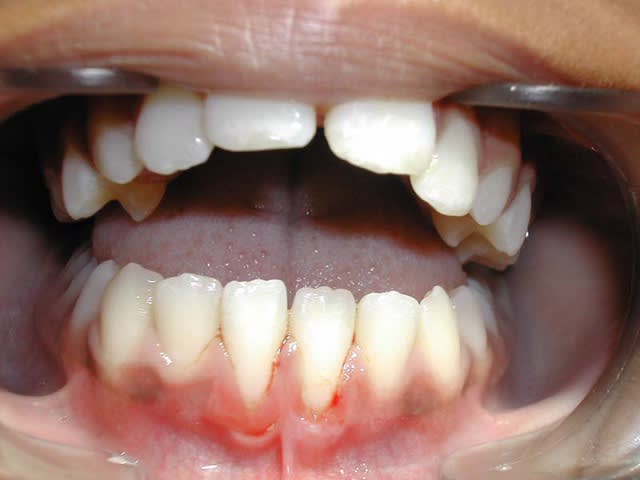

12 ans. Sexe F.

Voici un cas de béance associé à un Pb. paro sur 31/41

Est-ce qu’un traitement ODF. ne vas pas aggraver cette perte de gencive attaché (et osseuse),

et faut-il faire des extractions pour replacer 31/41 dans le massif osseux et arrêter cette récession ?